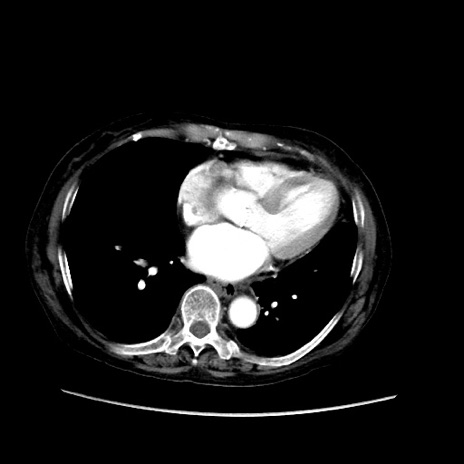

冠状断像

【症例】80歳代 女性

【主訴】腹部膨満感

【現病歴】他院にて肝硬変にてフォロー中。1週間前から便秘、腹部膨満感、臍部腫瘤あり受診となる。

【既往歴】肝硬変

【身体所見】腹部膨隆あり、皮膚変化なし、疼痛なし。

【データ】WBC 4600、CRP 0.25